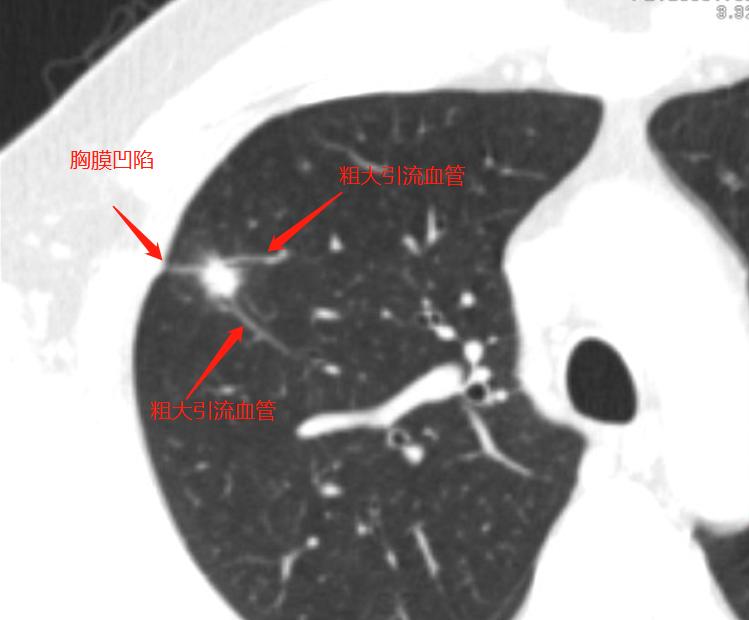

薄层高分辨三维重组图片

妥妥的恶性征象,令人心惊胆寒

影像学检查特点:右肺上叶尖段实性结节,大小1.2cm×1.1cm×1.0cm,分叶毛刺、胸膜牵拉,最主要的是有两个大的引流血管汇聚,诊断为恶性病变还需要理由吗?不需要理由。这种征象哪个医生也不敢说一定是良性的。建议活检应该是最好的选择。